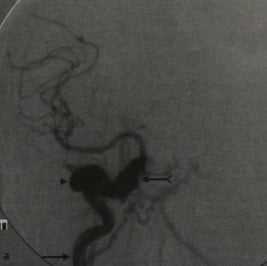

Кортикокавернозная фистула. ЦСА, заднепередняя (а) и латеральная проекции (b). Фаза раннего артериального наполнения (ВСА - стрелка) кавернозного синуса (раздвоенная стрелка), дренирующегося в оба каменистых синуса. Расширенная верхняя глазная вена (наконечник стрелки).

5. Ангиография при травматической каротидно-каверной фистуле:

• Традиционная:

о Раннее заполнение контрастом КС + путей оттока, включая:

- Ретроградное заполнение контрастом ВГВ, угловых + лицевых вен

- Контралатеральный КС

- Каменистые синусы → внутреннюю яремную вену(ы)

о Снижение или отсутствие антеградного кровотока во ВСА за пределами фистулы, зависит от размера дефекта ВСА

6. Рекомендации по визуализации:

• Лучший инструмент визуализации:

о ЦСА является окончательным методом исследования

о КТ/КТ-ангиография могут помочь в постановке предположительного диагноза; для его подтверждения и последующего лечения необходима ЦСА